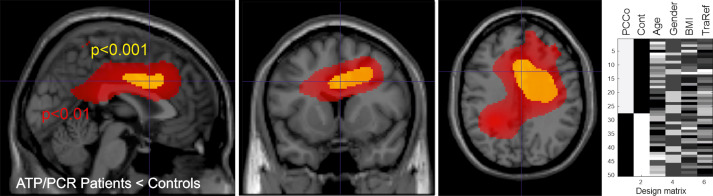

Eine neue Studie (Weber-Fahr et al., 2026) zeigte, dass in bestimmten Hirnregionen von Long COVID-Patienten das Verhältnis von ATP (dem Energie-Molekül) zu Phosphokreatin gestört ist – ein direkter Hinweis auf Energiemangel. Weniger ATP korrelierte mit schlechteren kognitiven Leistungen.

Weber-Fahr-et al., 2026

Weber-Fahr, W.; Dommke, S.; Sack, M.; Alzein, N.; Becker, R.; Demirakca, T.; Ende, G.; Schilling, C. Reduzierte ATP-zu-Phosphokreatin-Verhältnisse bei neuropsychiatrischen Post-COVID-Symptomen: Evidenz aus der 31P-Magnetresonanzspektroskopie. Biological Psychiatry , 2026. https://doi.org/10.1016/j.biopsych.2026.01.004